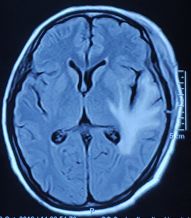

水肿消退,中线基本回位

术后恢复较好,复查核磁提示肿瘤切除满意,水肿明显消除,中线基本回位。病检结果提示血管瘤型脑膜瘤,WHO Ⅰ级。